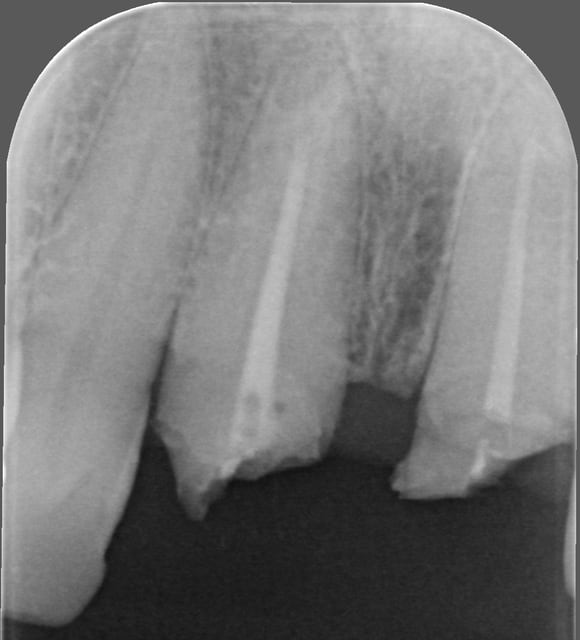

Dans la technique du rouleau, il me semble que le lambeau doit être de demi épaisseur et que les incisions de décharges verticales doivent être à distance des papilles pour les préserver. Ce qui ne semble pas être le cas là ( peine épaisseur pour retirer les vis...).

On va reprendre par le début, dans un cas comme ça:

avant la greffe, incision au disque de 12 à 22, incision de décharges autour de l'épine nasale, ensuite PAS d'expansion à l’ostéotome cylindrique, mais au tatum D1 au maximum, ou un plat, en douceur, en maintenant fermement l'os entre le pouce et l'index, ce qui n'est pas simple vu la qualité de l'os, et ensuite, si besoin en apicale greffe ou ROG que tu domine parfaitement d'ailleurs.

Comme tu aimes bien 2 ou 3 couche de prf par dessus et roule ...

la photo 2: désépithélialisation à la fraise diam pour faire une technique du rouleau?

perso, j'aurais probablement opté pour un conjonctif enfoui et réalisé un lambeau avec préservation des papilles au niveau des latérales...mais c'est peut être pas une bonne idée non plus et il y a peut être encore plus efficace et prédictible...